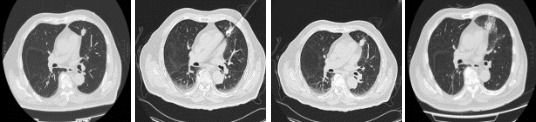

上海医生仅用35分钟一针消融病灶 机器人导航精准治疗!近日,上海市东方医院肿瘤科周彩存教授团队成功为一名高龄、肺功能基础差且病灶紧贴心脏的肺癌患者实施了机器人辅助下经皮穿刺消融手术。该案例不仅展示了团队在高危复杂部位肿瘤微创治疗领域的领先水平,还体现了学科在胸部肿瘤领域技术融合、团队协作与培训推广等多方面的系统化成果。数月前,科室获评“中国医师协会肿瘤消融治疗技术培训基地”,并于去年年底牵头成立东方胸部肿瘤诊疗中心,致力于打造全病程、多学科融合的诊疗高地。

77岁的陈老伯是一位刚走下手术台不久的“抗癌老兵”。1年半前,他经历了前列腺癌根治术,本以为可以安享晚年。然而,在最近的一次术后随访PET-CT检查中,医生发现他左肺上叶那颗原本“沉睡”的结节突然代谢增高,这意味着恶性肿瘤再次找上了门。尽管陈老伯的肺部病灶尚属早期,但其位置紧邻心脏,随呼吸与心跳同步移动,传统消融因易损伤心脏及大血管,风险极高。面对这一困局,陈老伯在家属陪同下辗转求医,最终求助于周彩存教授团队。

周彩存教授团队在充分评估后认为,病灶虽不大,但位于心脏旁“生命禁区”,临近重要心脏结构和大血管、大气道,任何物理局部处理手段都有一定风险。为此,团队决定启用穿刺手术导航定位系统(简称RC120),凭借其“CT影像与智能传感一体化”技术,解决传统定位方式的痛点,为陈老伯的肺部诊疗提供了更精准、更安全、更便捷的选择。